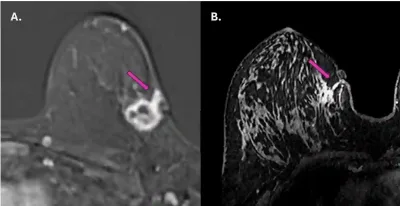

- A 2025 study used magnetic resonance imaging (MRI) to assess whether the cancer had spread along the path of a previous needle biopsy in a group of 62 patients with breast cancer. In three of them (4.8%), cancer cells were found growing in the biopsy tract, sometimes reaching the skin and subcutaneous tissue (Figure 1). These findings were confirmed by ultrasound and repeat biopsy.

Figure 1. Magnetic resonance imaging (MRI) scans showing tumour spread along the needle biopsy path in two breast cancer patients (purple arrows). In both cases, the cancer appears to have extended from the original tumour site toward the skin and surrounding tissue along the path created by the biopsy needle. Source: Fleury et al. (2025), Cureus.